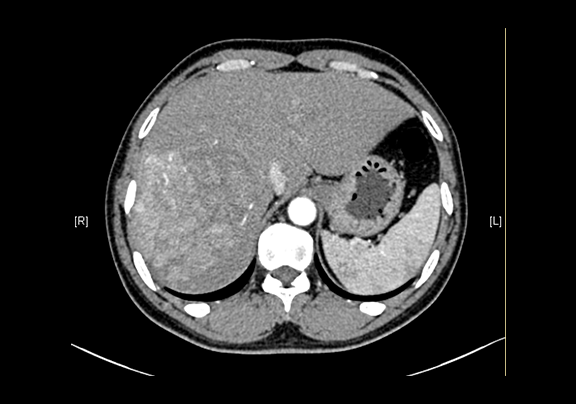

现病史:患者20余天前查体,行腹部超声检查时发现:肝右叶低回声结节,大小约5.8*4.7cm,无腹痛、腹胀,无腰背部放散痛、皮肤巩膜无黄染,无寒战、高热,无咳嗽、咳痰、胸闷、气短,无恶心、呕吐,无腹泻、血便,无尿频、尿急、尿痛、血尿。上腹部动态三维成像(增强)CT检查示,肝右后叶上段占位性病变,肿瘤性病变。

下腹部增强CT示:肝右后叶上段占位性病变,肿瘤性病变,考虑肝癌合并出血可能性大,肝多发小囊肿

术前CT检查:

动脉期

静脉期

平衡期